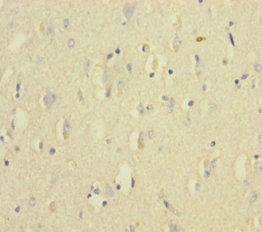

應(yīng)用范圍:ELISA, IHC

Application Recommended Dilution IHC 1:20-1:200 -